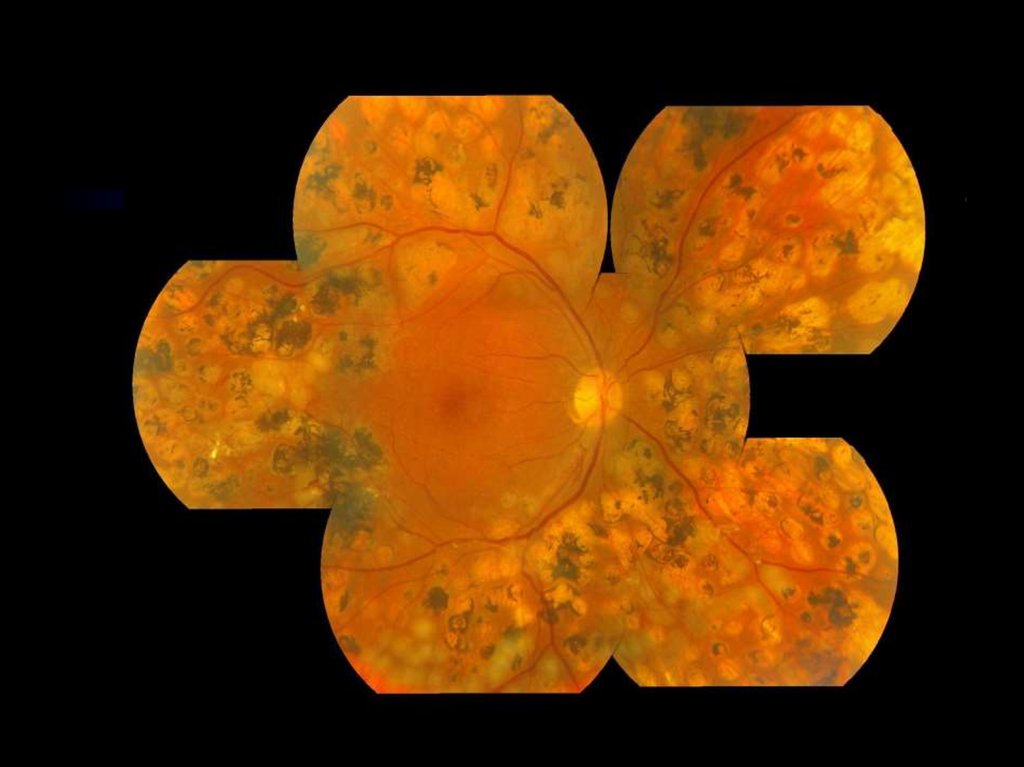

СЕМИПОЛЬНОЕ ФОТОГРАФИРОВАНИЕ СЕТЧАТКИ

ПРЕПРОЛИФЕРАТИВНАЯ ИЛИ ПРОЛИФЕРАТИВНАЯ РЕТИНОПАТИЯ БЕЗ МАКУЛЯРНОГО ОТЕКА

СТАНДАРТНАЯ СХЕМА ВЫПОЛНЕНИЯ ПАНРЕТИНАЛЬНОЙ ЛАЗЕРКОАГУЛЯЦИИ

КРИТЕРИИ ЭФФЕКТИВНОСТИ ПАНРЕТИНАЛЬНОЙ ЛАЗЕРКОАГУЛЯЦИИ

СОСТОЯНИЯ, ТРЕБУЮЩИЕ БОЛЕЕ «АГРЕССИВНОГО» ЛАЗЕРНОГО ВОЗДЕЙСТВИЯ

ПРОЛИФЕРАТИВНАЯ РЕТИНОПАТИЯ С МАКУЛЯРНЫМ ОТЕКОМ

СЕМИПОЛЬНОЕ ФОТОГРАФИРОВАНИЕ СТАНДАРТНЫХ ПОЛЕЙ СЕТЧАТКИ

ХАРАКТЕРИСТИКА ГРУППЫ

ПОКАЗАТЕЛИ ЛИПИДНОГО ОБМЕНА ДО И ПОСЛЕ НАЗНАЧЕНИЯ ФЕНОФИБРАТА

ПРОГРЕССИРОВАНИЕ РЕТИНОПАТИИ

ЛАЗЕРНАЯ КОАГУЛЯЦИЯ СЕТЧАТКИ